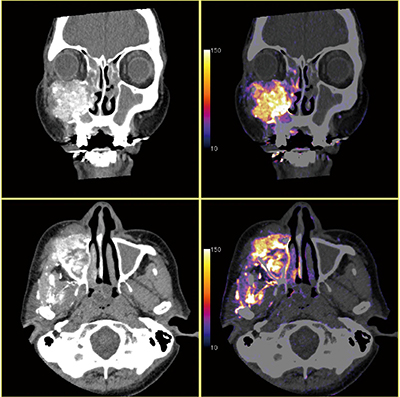

症例1 上顎洞がん、栄養血管の把握

腫瘍に対する栄養血管の塞栓治療時に、サブトラクション技術による“Iodine Map”が有用だった症例。Iodine Mapによって、腫瘍内に染まらない箇所が存在していることを客観的に把握でき、異なる栄養血管の関与が迅速に判断できた。ボリュームスキャンによって寝台を動かさず0.5秒で撮影が完結し、高速かつ安全な手技が可能であった。